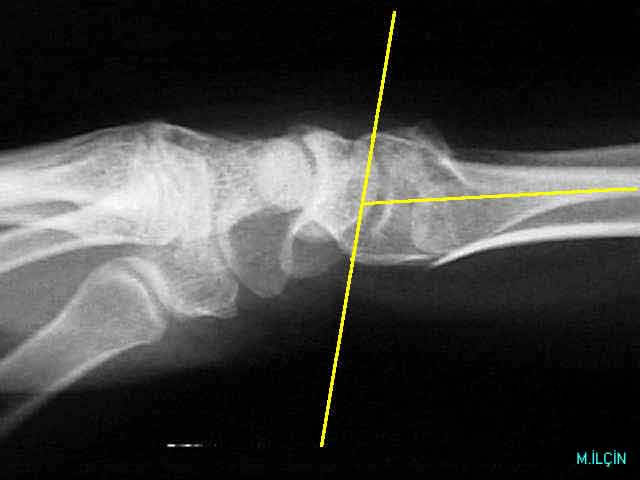

FG/distal.jpg